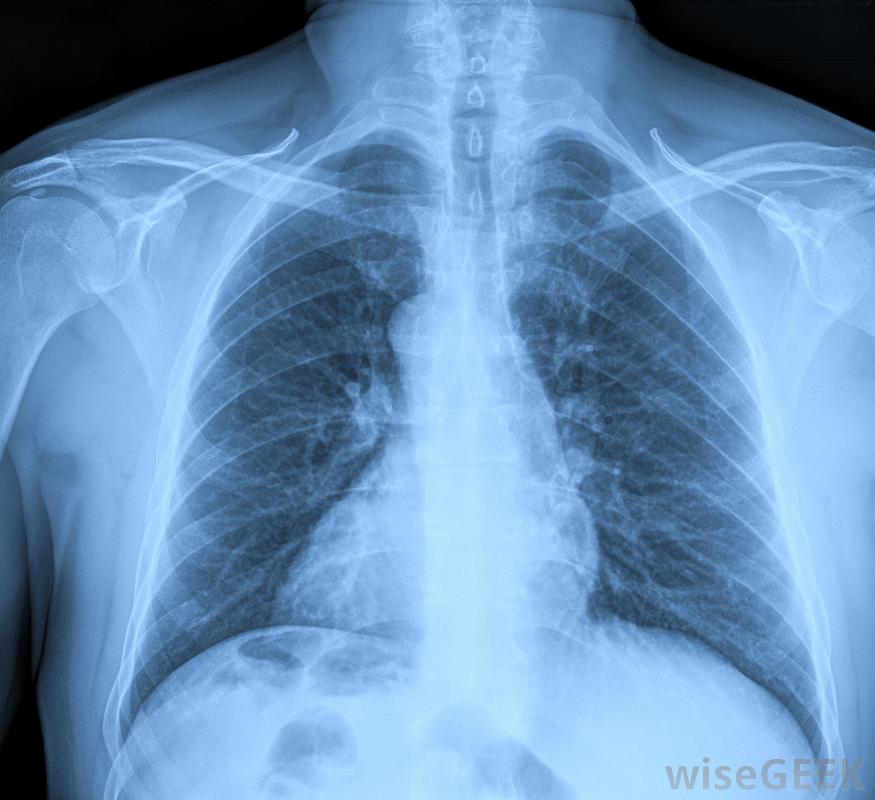

胸部X光片可确认膈肌畸形有时医生可以在胎儿还处于子宫内时,通过超声波和其他影像学检查来发现Bochdalek疝气。然而,在大多数情况下,直到他或她出生后才知道婴儿有严重的问题,婴儿可能表现出呼吸困难和心率加快的迹象。他或她的皮肤可能因为血液中缺氧而呈蓝色。婴儿也可能是跛足的,不能哭也不能睁开眼睛。一组医生通过体格检查可以很快诊断出Bochdalek疝气。当器官在胸部太高时,腹部通常会感到空荡荡的,很容易被压缩。医生也可以用听诊器听到胸部的肠道噪音。如果患者足够稳定,可以进行胸部x光或电脑断层扫描确认膈肌畸形。治疗的首要目标是通过氧疗或心肺复苏来稳定呼吸。如果心脏功能不正常,为了保持血液循环,可能需要一台旁路手术。修复博克达莱克疝是一项精细的手术,需要切开胸腔,用手固定肠道、肾脏、胃和其他器官,然后缝合膈膜上的洞,闭合手术伤口。24小时不停在手术后的几天里,监测和治疗是很重要的,以确保不会出现并发症。